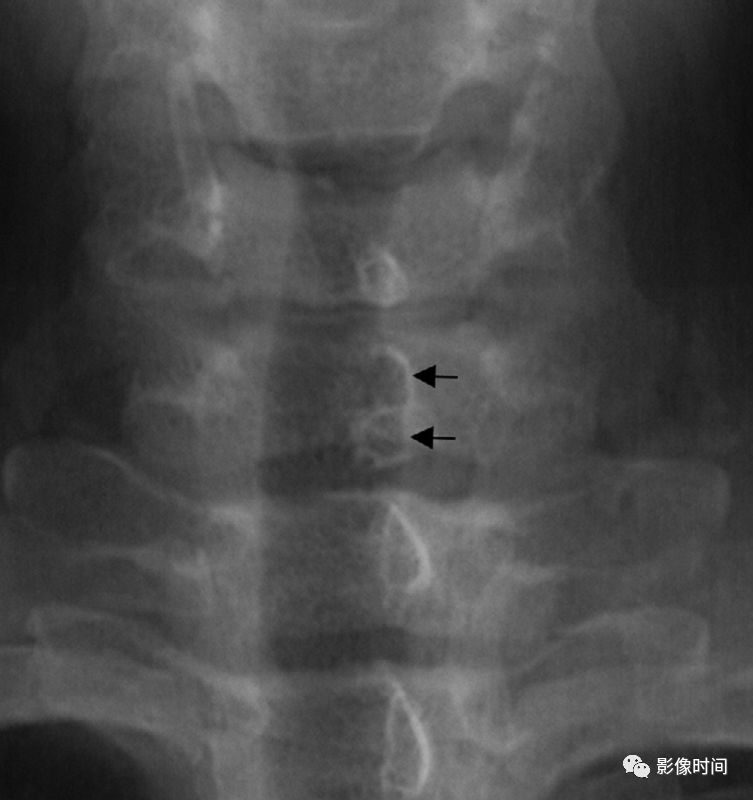

15椎弓根征

椎弓根征,又称眨眼猫头鹰征(Winking owl sign)

本征指的是在脊柱正位 X 线片上,一侧椎弓根投影消失,为「闭一只眼」(箭示),另一侧椎弓根投影存在,为「睁一只眼」(圈),相应棘突类似喙,总体形似一只眨眼的猫头鹰。

典型病例

病例 1. 女,37 岁,腰痛 4 月余,肺癌转移。腰椎正位片,示第 3 腰椎右侧椎弓环影破坏消失。

病例 2. 胸椎转移瘤。正位 X 线片示胸 11 左侧椎弓根投影消失(白箭),右侧椎弓根影存在(黑箭),形似眨眼的猫头鹰。

16跳跃征

在脊椎的 MR 各序列中,脊柱的椎体和/或附件多节段受累时,呈现病变脊椎之间有正常脊椎(箭示)的不连续改变,称为跳跃征。常见于脊椎转移瘤。

67 岁男性,前列腺癌脊椎转移。磁共振 T1WI 及 T2WI 图像示多椎体多发病灶(箭示),大小不等,分布呈现跳跃征。